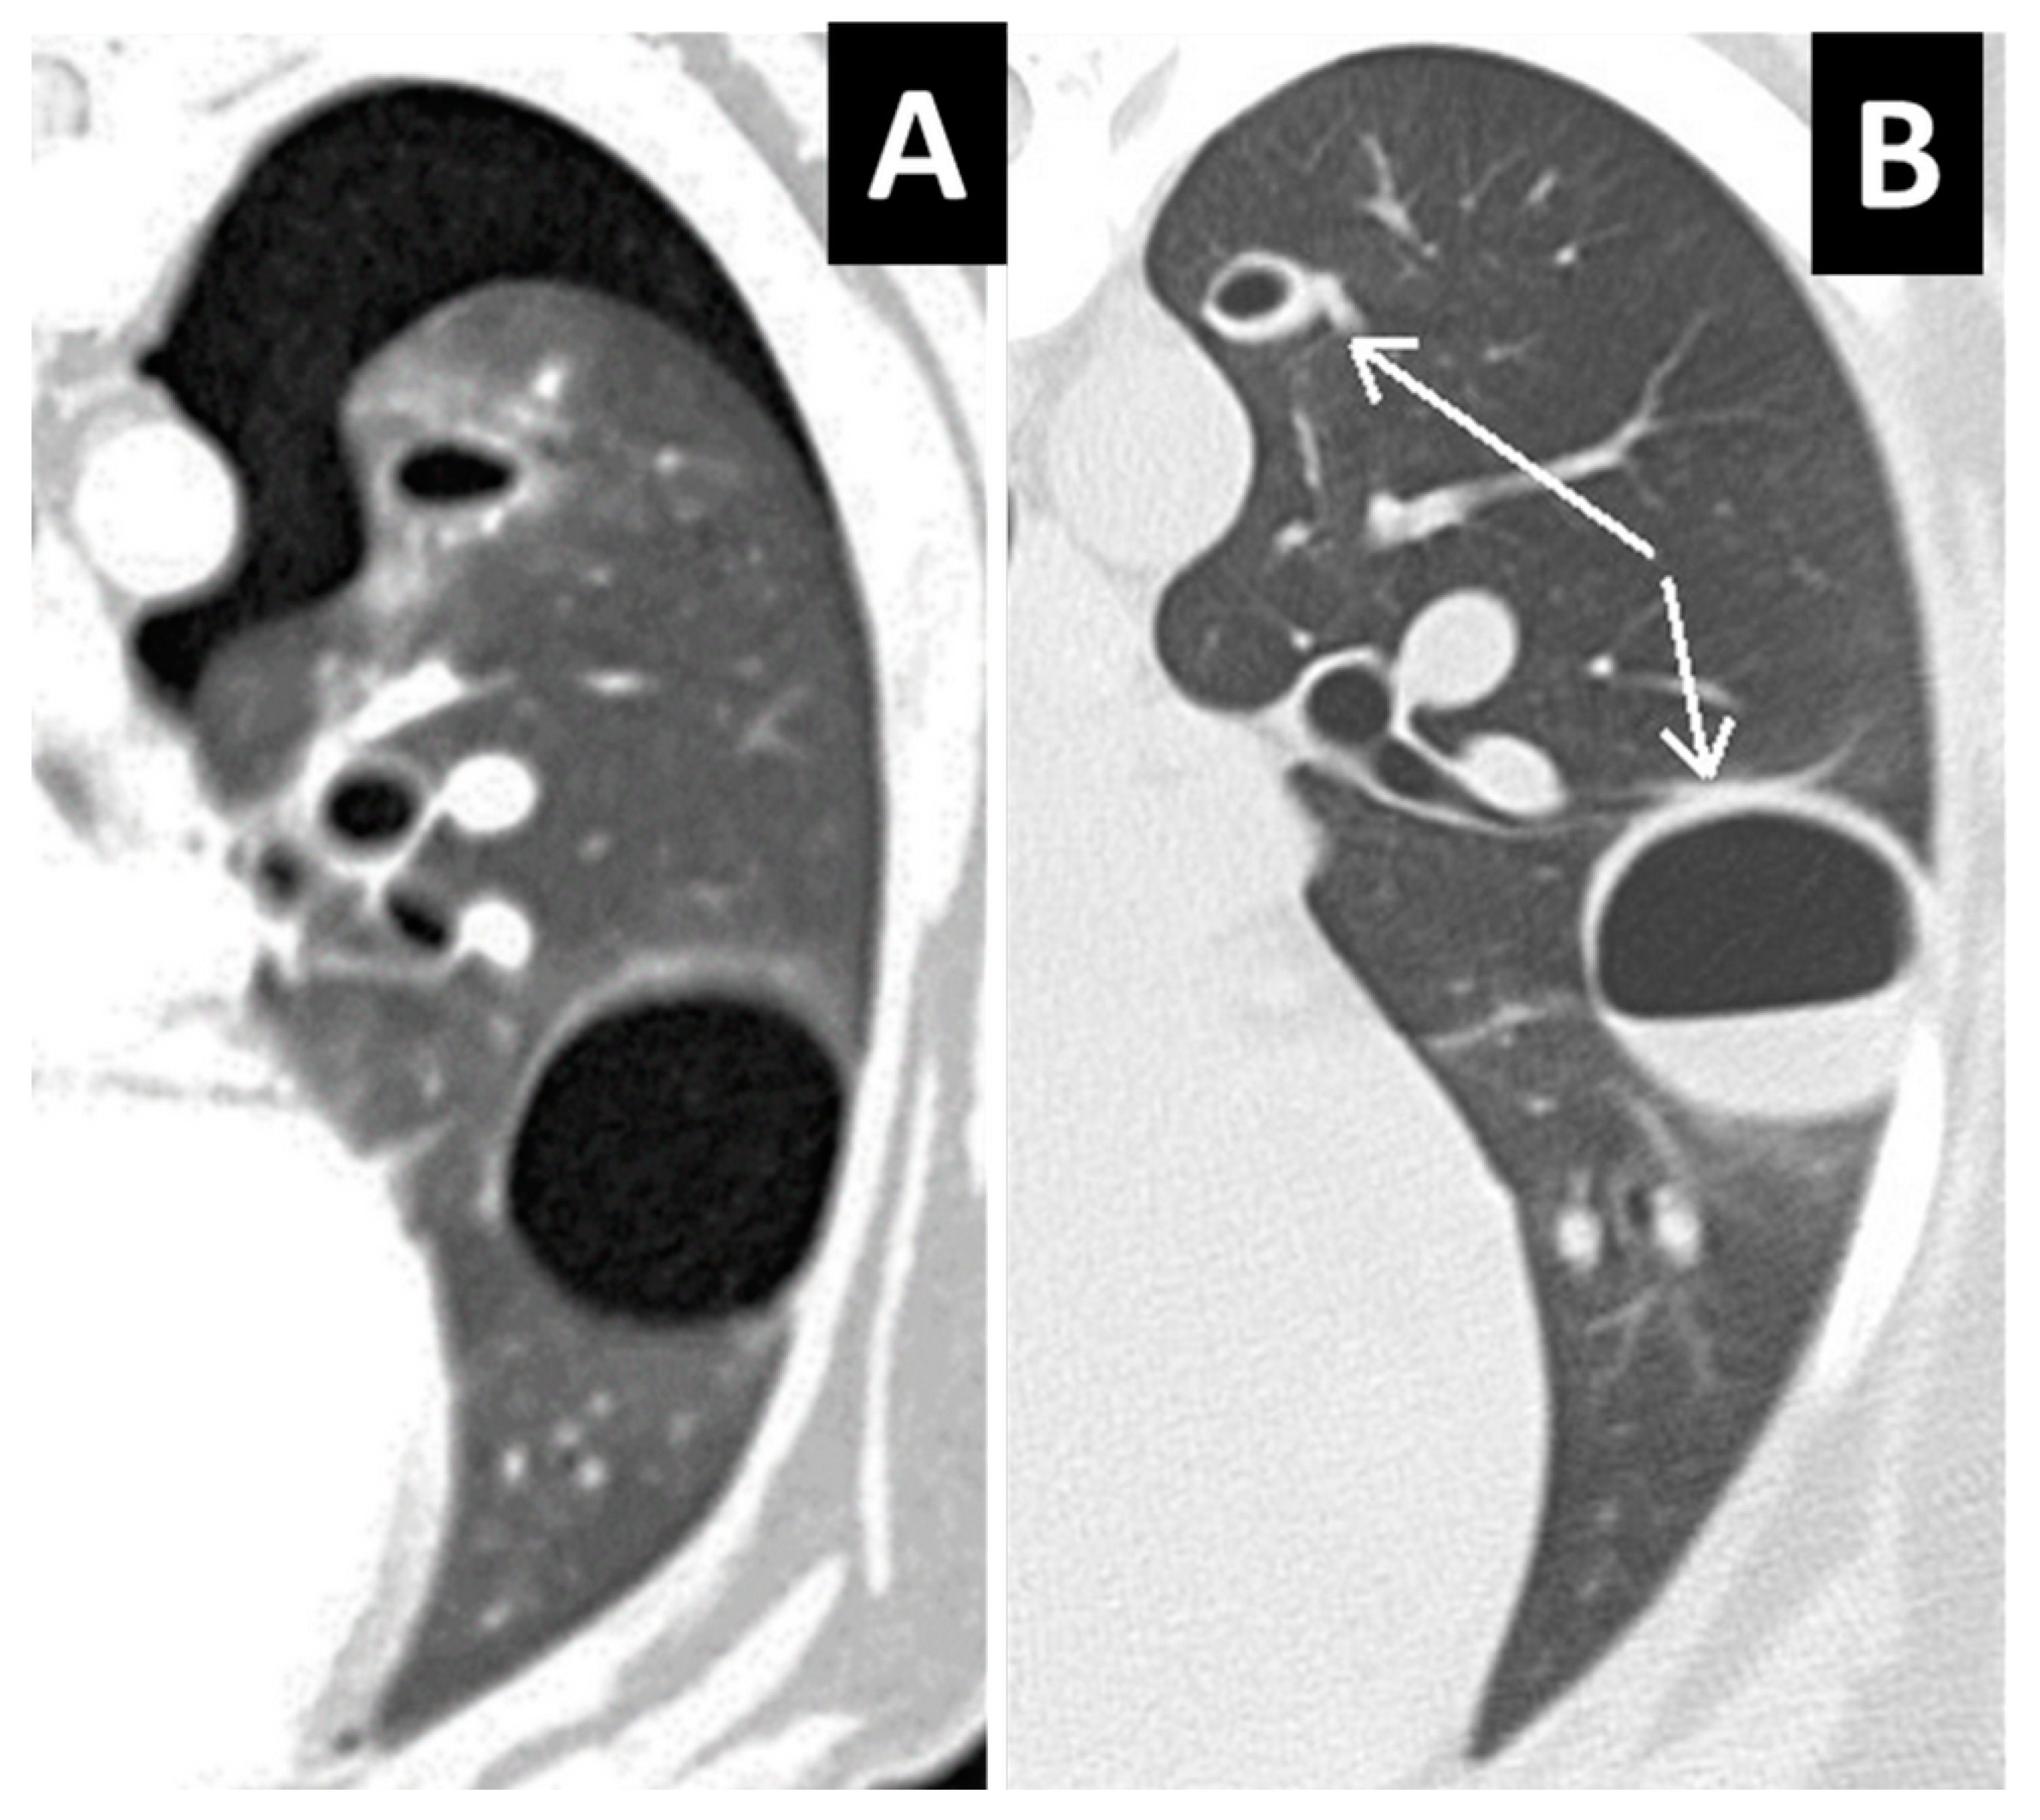

Figure 8.

(A,B) Transverse and right-parasagittal views of the thorax in a patient with subpleural lung laceration and massive pneumothorax, with subsequent lung collapse.

One or more follow-up CT studies were available in four cases from 2 days to one month after the initial CT examination. In follow-up CT studies, lesions showed increasing fluid content over time (Figure 7). Complications of lung lacerations were observed in two cases. One dog showing several lung lacerations in the right caudal lobe one hour after trauma underwent lobectomy few days after admission for the abscessation and pneumonic involvement of that lobe. Another dog showed a lung collapse due to massive pneumothorax for a ruptured subpleural lung laceration (Figure 8). In this case, a chest drainage system placed for few days allowed the lung to be pulled up against the parietal pleura and the dog was discharged to its home in a stable condition.